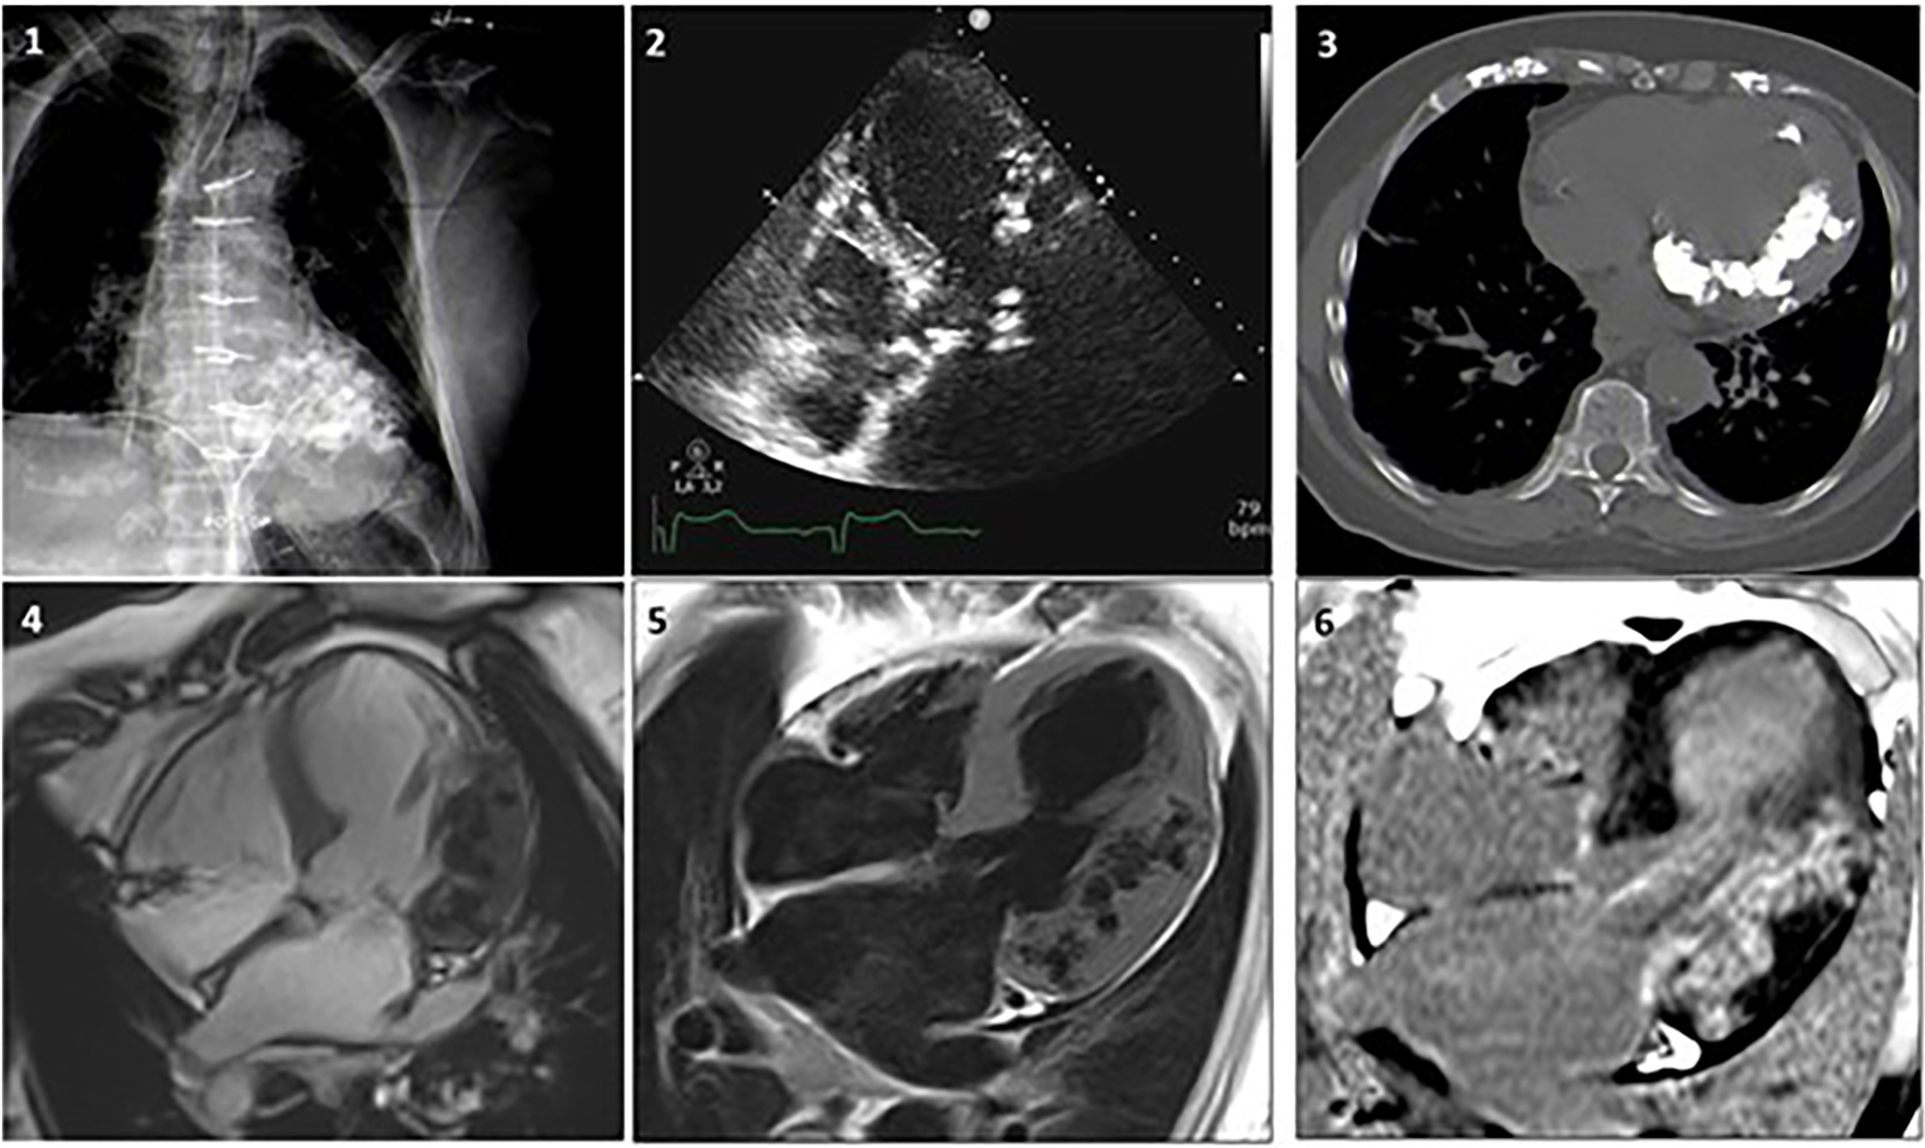

In Figure 6, a clinical case from Sozzi et al (21), shows the additional diagnostic role of cardiac CT and CMR for evaluation of MC is shown. An 80-year-old woman with known CAD, with a history of coronary artery bypass surgery underwent chest x-ray, echocardiography, cardiac CT and CMR to ascertain the etiology of her MC. In this case the multimodality imaging analysis excluded previous MI, myocarditis and calcium-phosphate disorders. A dystrophic etiology was considered. The pathological mechanism for dystrophic calcifications is related to calcium deposition in any dead and dying myocardial tissues.

Case 1. A woman, 80 year-old, with CAD underwent revascularization through coronary artery bypass grafiting. (1) Chest x-ray showing a diffuse hypodense lobulated area in the left ventricle. (2) Echocardiogram revealing diffuse aortic and mitral calcifications with mild stenosis, marked septum and antero-lateral asymmetric hypertrophy, with extensive antero-lateral calcifications. (3) Non-contrast CT MPR axial-view presents widespread calcifications in the left ventricular wall extended to the mitral-aortic annulus and both coronary arteries. (4) CMR SSFP 4-chamber view showing lateral and antero-lateral wall thickening with areas of intra-myocardial low signal, surrounded by normal myocardium. Coronary angiography documented significant disease that required revascularization. (5) FSE T1 weighted-spin-echo4-chamber view is confirming the localization of lateral and anterolateral wall thickening with areas of low-signal. (6) After contrast gadolinium injection an extensive area of intra-myocardial hypersignal (hyperenhancement) is shown in the lateral wall. Adapted with permission from Sozzi et al. (21), licensed under CC BY 4.0.